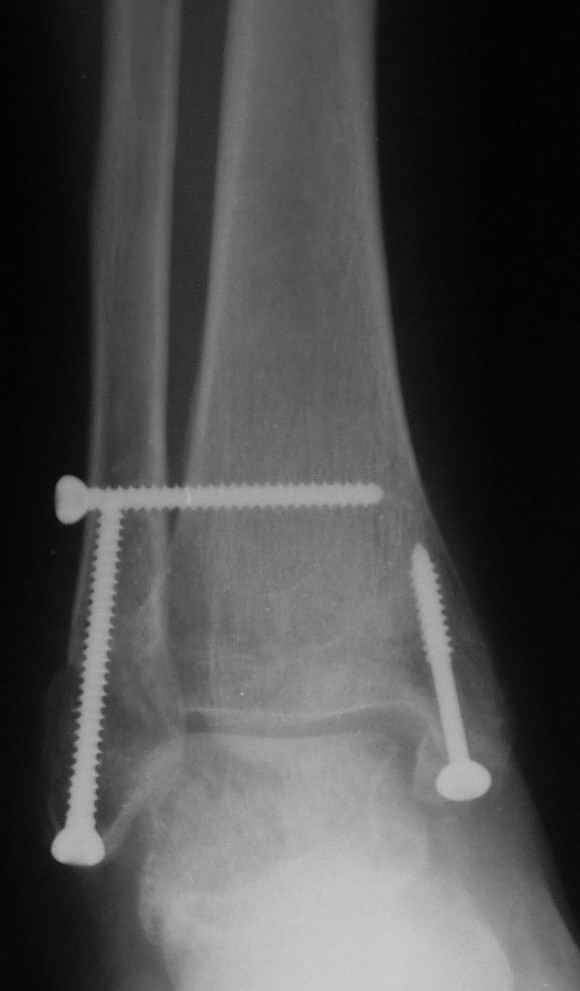

12 января прямой

12 января боковой

12 января трехчетвертной